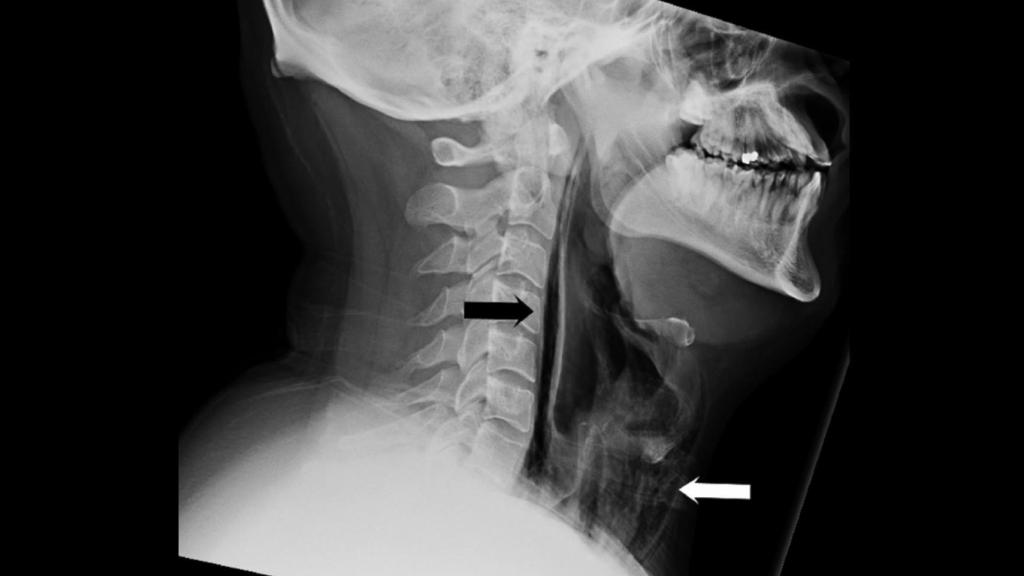

Las lesiones y la entrada de aire en la garganta del paciente.

Las lesiones y la entrada de aire en la garganta del paciente. Yang W, et al. BMJ Case Rep 2018.

El desafortunado protagonista del caso es un hombre de 34 años que acudió al Hospital Universitario de Leceister, Reino Unido, tras intentar "tragarse" un estornudo. Por motivos que permanecen ignotos para preservar su confidencialidad, se tapó la nariz y la boca al momento de estornudar. En ese momento sintió una sensación de "reventón" (popping) en el cuello, que a continuación comenzó a hincharse. El paciente empezó a sufrir un agudo dolor de garganta que le impedía tragar y una ronquera severa que apenas le permitía hablar.

La inspección médica reveló un crepitar en su respiración, un sonido burbujeante de su cuello a su caja torácica que indicó a los especialistas que se había infiltrado aire en su tejido y músculos del pecho. Una tomografía confirmó la presencia de enfisemas - bolsas de aire - en su cuello, en las zonas de la tráquea y la laringe. También se observó la presencia de neumomediastino, la infiltración de aire en el mediastino, la región torácica entre ambos pulmones.

El equipo de cirugía oral y maxilofacial dirigido por la doctora Wanding Yang determinó que se había desgarrado la faringe por bloquearse las vías aéreas al estornudar a la altura del seno piriforme. Esta ruptura de la parte posterior de la garganta ya había sido observada como consecuencia de un trauma violento provocado por tos intensa, vómito o náuseas, pero es la primera vez que se describe como efecto de un estornudo. La situación era grave: el paciente corría el riesgo de contraer una infección tanto en el cuello como en el tórax (mediastinitis).